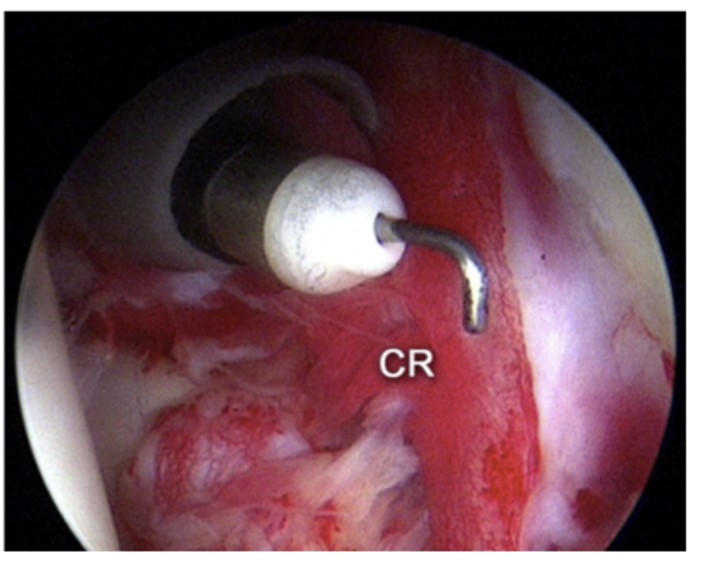

反復性肩関節脱臼

反復性肩関節脱臼とは、一度肩関節が脱臼した後、再発を繰り返す状態を指します。肩関節が脱臼すると、肩関節を支える組織が損傷し、再発しやすくなるため、日常生活やスポーツ活動に支障をきたすことがあります。

外傷(スポーツによる怪我など)で肩関節が一度脱臼すると、関節唇や靭帯が損傷し、肩関節が不安定になります。初回の脱臼では固定、リハビリテーションでの治癒をめざします。2回目の脱臼をすると、3回目以降に脱臼する確率が50%以上となり、軽い外力(寝返り、腕を後ろに組むなど)で脱臼を繰り返すようになります。この状態を反復性肩関節脱臼と言います。

再発を繰り返す場合は手術が必要となることが多く、手術では、損傷した組織を縫合したり、骨を補強したりすることがあります。一般的に、関節唇と言われる肩関節の吸盤の働きをしている構造物がこの病態にもっとも関与していると言われており(図11)、手術では一般的に関節唇を関節鏡手術で修復します(図12)。